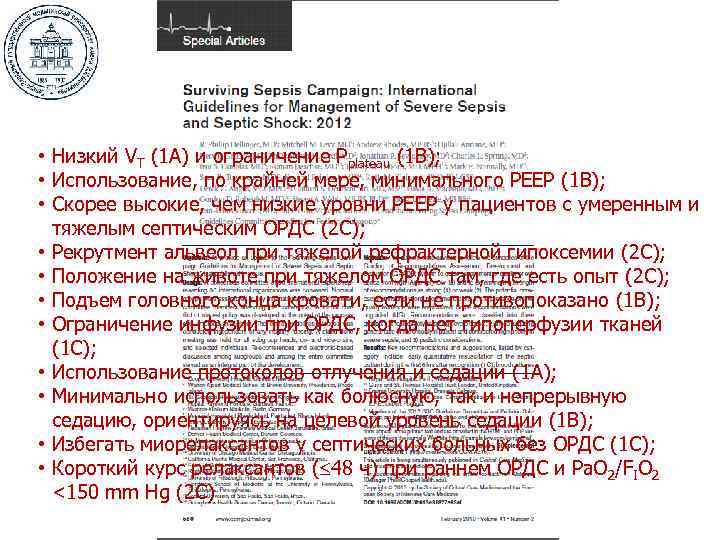

• Низкий VT (1 A) и ограничение Рplateau (1 B); • Использование, по крайней мере, минимального РЕЕР (1 B); • Скорее высокие, чем низкие уровни РЕЕР у пациентов с умеренным и тяжелым септическим ОРДС (2 C); • Рекрутмент альвеол при тяжелой рефрактерной гипоксемии (2 C); • Положение на животе при тяжелом ОРДС там, где есть опыт (2 C); • Подъем головного конца кровати, если не противопоказано (1 B); • Ограничение инфузии при ОРДС, когда нет гипоперфузии тканей (1 C); • Использование протоколов отлучения и седации (1 A); • Минимально использовать как болюсную, так и непрерывную седацию, ориентируясь на целевой уровень седации (1 B); • Избегать миорелаксантов у септических больных без ОРДС (1 C); • Короткий курс релаксантов ( 48 ч) при раннем ОРДС и Pa. О 2/FIO 2 <150 mm Hg (2 C)

• Низкий VT (1 A) и ограничение Рplateau (1 B); • Использование, по крайней мере, минимального РЕЕР (1 B); • Скорее высокие, чем низкие уровни РЕЕР у пациентов с умеренным и тяжелым септическим ОРДС (2 C); • Рекрутмент альвеол при тяжелой рефрактерной гипоксемии (2 C); • Положение на животе при тяжелом ОРДС там, где есть опыт (2 C); • Подъем головного конца кровати, если не противопоказано (1 B); • Ограничение инфузии при ОРДС, когда нет гипоперфузии тканей (1 C); • Использование протоколов отлучения и седации (1 A); • Минимально использовать как болюсную, так и непрерывную седацию, ориентируясь на целевой уровень седации (1 B); • Избегать миорелаксантов у септических больных без ОРДС (1 C); • Короткий курс релаксантов ( 48 ч) при раннем ОРДС и Pa. О 2/FIO 2 <150 mm Hg (2 C)